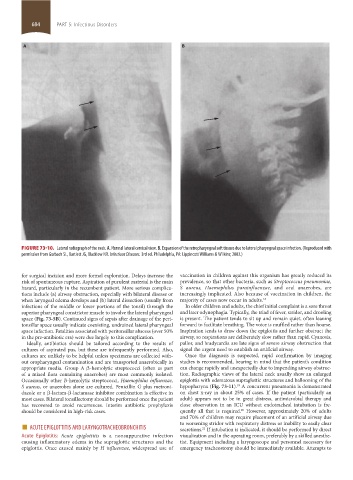

FIGURE 73-10. Lateral radiograph of the neck. A. Normal lateral cervical view. B. Expansion of the retropharyngeal soft tissues due to lateral pharyngeal space infection. (Reproduced with

permission from Gorbach SL, Bartlett JG, Blacklow NR. Infectious Diseases. 3rd ed. Philadelphia, PA: Lippincott Williams & Wilkins; 2003.)